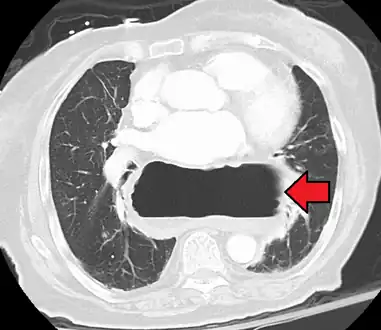

A hiatal hernia as seen on CT

A large hiatal hernia as seen on CT imaging

A large hiatal hernia as seen on CT imaging- As seen on ultrasound[9]